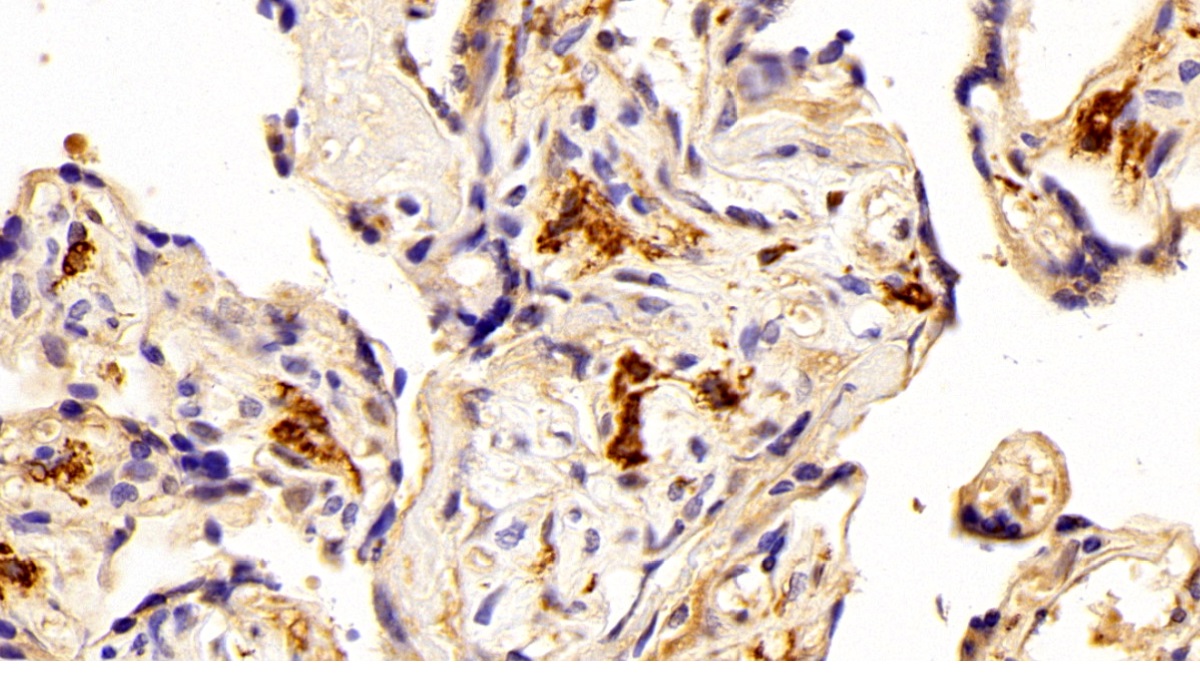

Использование высококачественных первичных антител является неотъемлемым условием получения точных и воспроизводимых результатов в современных научных исследованиях. Например, в рамках онкологического исследования удалось достоверно идентифицировать экспрессию белка PD-L1, что сыграло ключевую роль в оценке потенциальной эффективности иммунотерапии. Применение надежных антител обеспечило стабильность сигнала и высокую специфичность детекции, что позволило получить данные, пригодные для публикации в рецензируемых научных изданиях.

Способы применения первичных антител

Первичные антитела используют в разных методах: от вестерн-блоттинга до иммунофлюоресценции и проточной цитометрии. Всё решает подготовка: нужно грамотно выбрать буфер, точно рассчитать, сколько продукта добавить, и не затянуть с инкубацией. Например, в вестерн-блоттинге без правильной блокировки мембраны фон может всё испортить, а в иммунофлюоресценции фиксация клеток решает, будет ли сигнал ярким. Мы не просто продаём реагенты, а помогаем довести эксперимент до результата: подбираем реагенты и даём советы по методам, если есть специфика в протоколах производителя. Нужен особый подход? Оформите спецзаказ по ссылке — мы найдём решение для вашего проекта.